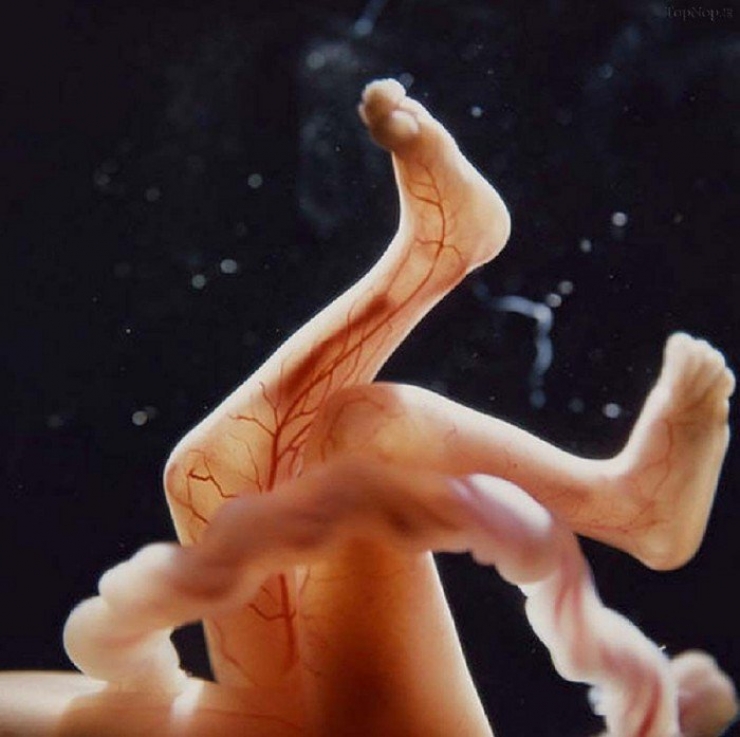

16: Au bout de 16 semaines (4 mois)...

17: Les vaisseaux sanguins et notamment les artères commencent à se former complètement

18: Au bout de 18 semaines, le foetus peut entendre certains sons venant de l'extérieur